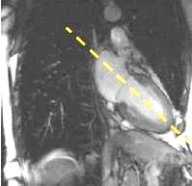

On the 2-chamber view, prescribe and acquire a long axis 4-chamber view using an ungated 2D FIESTA.

Figure 3. Long axis 2-chamber viewFigure 4. 4-chamber view